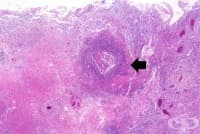

Казеозна некроза

Казеозна некроза е разновидност на коагулационната некроза. При нея загиват тъкани и значителен брой...